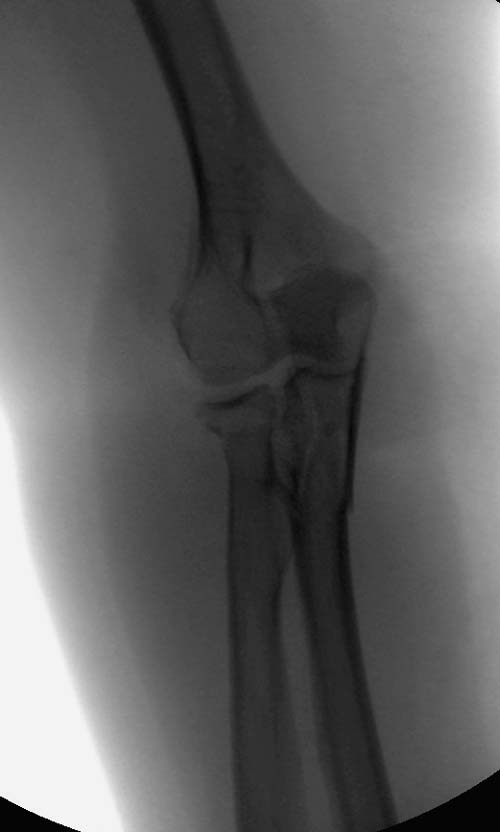

В первом случае перелом Монтеджи, где доперационно сделано оценка положения головки к остальным элементам под рентгеном. Учитывая правильность взаимотношении произведена фиксация только локтевого отростка, Второй случай, заменена на протез, и третий, кроме фиксации головки - реконструкция capitellum латерального мыщелка.

На переломы головки луча надо обратить внимание, потому что головка луча является важным стабилизатором в локтевом суставе: удерживает от заднего вывиха и от боковых смещений. Изолированный перелом головки луча встречается очень редко и, в основном, в сопровождении с другими повреждениями, вывихом сустава, переломом Monteggia, венечного отростка или повреждением латерального лигамента.

Переломы по Mason первой степени без блокировки и смещение до 2х мм можно лечить в обычной косынке, или брейсом - консервативно. Перелом второй степени оперативно, а многооскольчатые переломы третьей степени лечатся заменой головки.